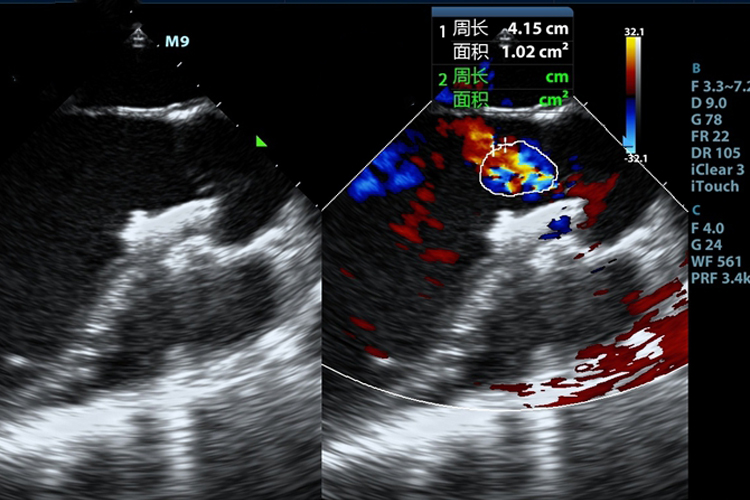

房间隔缺损彩超可见右心房、右心室的增大,还可见血流分流的频谱,可明确心脏并发畸形的位置。

房间隔缺损彩超可显示出房缺、右心房、右心室增大,肺动脉增宽。房间隔连续中断,并可见左向右血流分流频谱。